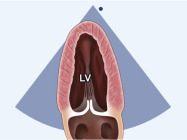

| 2.2. Mặt cắt trục dài cạnh ức khu trú vào thất trái

Cửa sổ siêu âm cạnh ức

Mặt cắt trục dài cạnh ức Đầu dò đặt tại bờ trái xương ức với marker hướng lên vai phải của bệnh nhân. Chùm siêu âm đặt vuông góc với thất trái. |

Nhĩ trái (LA)

Van hai lá (MV) Thất trái (LV) Đường ra thất trái (LVOT) Van động mạch chủ (AV) Vách liên thất (IVS) Thất phải (RV) |